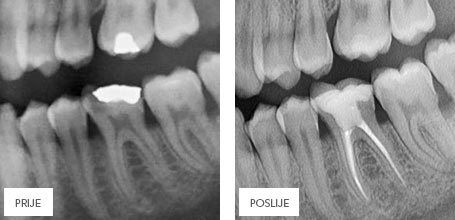

ЭНДОДОНТИЯ – ЛЕЧЕНИЕ КОРНЕВЫХ КАНАЛОВ ЗУБА

В результате кариеса или разрушения зуба бактериям открывается доступ к корневому каналу (пульпе), что ведет к воспалению, а иногда и к некрозу, которые могут распространиться и на соседние ткани. Если такой процесс уже начался, то необходимо удалить из канала воспаленую или некротичную ткань, чтобы предотвратить ослабление соседних тканей и потерю зуба. Такое лечение называется эндодонтическим (терапия каналов зуба), которое может быть проведено вручную или с помощью специальной аппаратуры.

После обработки и очищения каналов, они заполняются специальной пастой и гуттаперчевыми штифтами, с помощью которых каналы герметически закрываются и дальнейшее проникновение бактерий и возникновение инфекции становится невозможным.